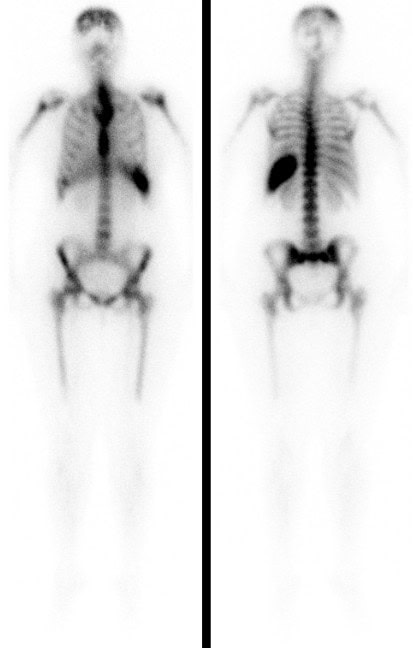

Das Knochenmark ist bei Erwachsenen auf das Stammskelett sowie die Rumpf-nahen Anteile der Oberarm- und Oberschenkelknochen begrenzt.

Ziel einer Knochenmarkszintigraphie ist die Darstellung des Knochenmarks in seiner Kontinuität und/oder seiner Ausbreitung. Die Kontinuität des Knochenmarks ist wichtig zum Ausschluss evtl. tumoröser oder infektiöser Raumforderungen im Knochenmark, die bei erheblichem Befall zu einer Verschiebung des Knochenmarks in die Peripherie führen können (sog. Knochenmark-Expansion).

Sofern es nicht um die Darstellung von unterer Brust- und oberer Lendenwirbelsäule geht, ist eine einfache und kostengünstige Szintigraphie mit Technetium-markierten Nanokolloiden möglich. Ansonsten muss die Untersuchung mit einem radioaktiv-markierten Granulozyten-Antikörper (Scintimmun™) erfolgen.